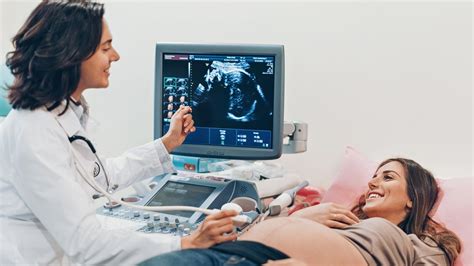

Počas morfologického ultrazvuku lekár detailne kontroluje všetky orgány a časti tela bábätka, aby sa uistil, že sa správne vyvíjajú. Medzi sledované oblasti patria:

- Hlava: Skúma sa obvod hlavy (HC) a biparietálny priemer (BPD), ako aj celková štruktúra mozgu a tváre, aby sa zistilo, či nemá dieťa napr. rázštep pery alebo podnebia. Sleduje sa jeho štruktúra a vývoj.

- Srdce: Hodnotí sa veľkosť štyroch komôr, správna funkcia chlopní, ako aj prietoky krvi. Lekár hodnotí jeho funkciu a štruktúru.

- Orgány brušnej dutiny: Kontroluje sa prítomnosť, tvar a funkčnosť orgánov ako sú pľúca, žalúdok, črevá, obličky, pečeň a močový mechúr.

- Končatiny: Lekár overuje prítomnosť a správny vývoj všetkých prstov na rukách a nohách.

- Chrbtica: Kontroluje sa jej celistvosť a správne uzatvorenie.

- Pohlavie dieťaťa: V tomto štádiu tehotenstva je už často možné s vysokou presnosťou určiť pohlavie dieťaťa.

Okrem detailného prehľadu orgánov sa počas morfologického ultrazvuku skenuje aj placenta, pričom sa hodnotí jej štruktúra a umiestnenie v maternici. Lekár tiež kontroluje množstvo plodovej vody.